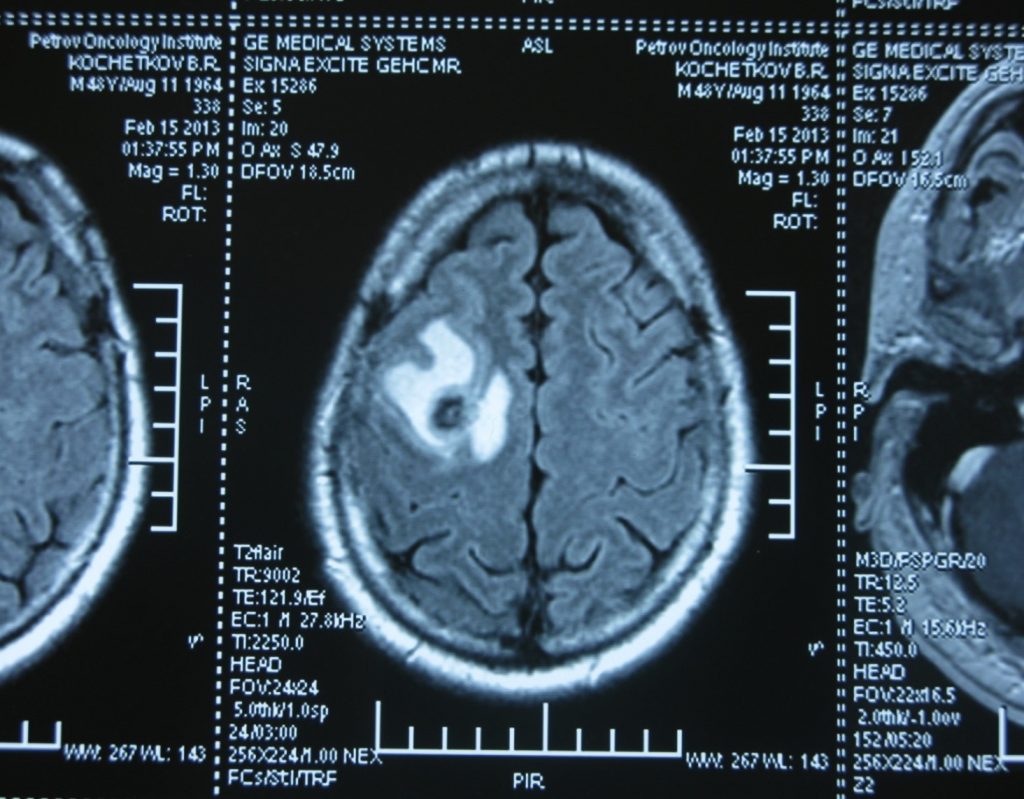

Стандартом диагностики герминогенных опухолей является  физикальный осмотр пациента,  сбор анамнеза и анализ крови на биологические опухолевые маркеры. К ним относятся АФП (альфа-фетопротеин), β -ХГЧ (β единица хорионического гонадотропина человека) и ЛДГ (лактатдегидрогеназа). В качестве уточняющих исследований проводится КТ органов брюшной полости и грудной клетки, либо УЗИ органов брюшной полости и рентгенография грудной клетки в двух проекциях. Также выполняют МРТ головного мозга, чтобы выявить наличие метастазов в нем. Орхофуникулэктомия - удаление яичка, выполняется с диагностической и лечебной целью.

04-1024x799.jpgМетастаз в головной мозг при герминогенных опухолях (МРТ головного мозга)